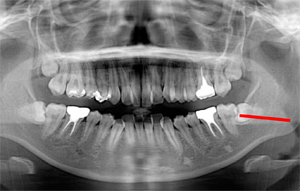

3. ほぼ真横にはえている

|  |

この状態の親知らずは生える事はありません。

見た目も歯茎の中や骨の中にうまっている為解りません。

歯科医院にてレントゲンを撮る事で親知らずがあるかないかが解りますので、一度レントゲンを撮って確認してみましょう。

症状として

- 歯ぐきが痛くなる

- 顎が痛くなる

- 口が開かなくなる

これらの諸症状が一度でも出た事がある方は、抜歯を考えた方が良いでしょう。